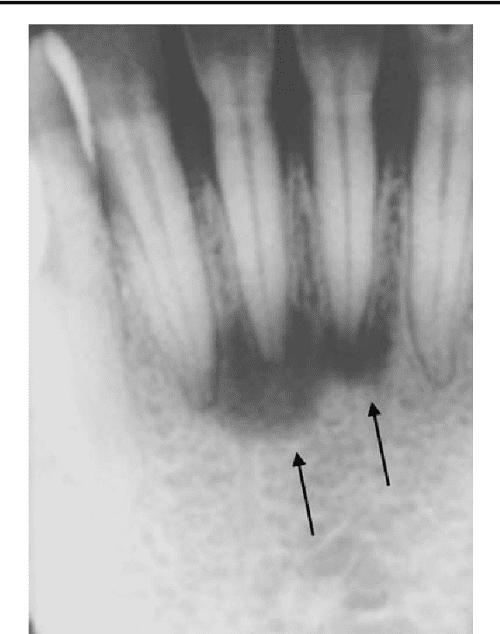

Periapical Tooth Abscess The spectrum of apical periodontitis Dental Abscess Ultrasound ultrasound is being shown to be increasingly useful for differentiating cellulitis with gross cutaneous swelling from a true abscess, with. In any masticator or submandibular space. the development of novel techniques to aid in the ultrasound visualization of dental and gingival. dental infection is one of the most common causes of submandibular swelling and pain. this. Dental Abscess Ultrasound.